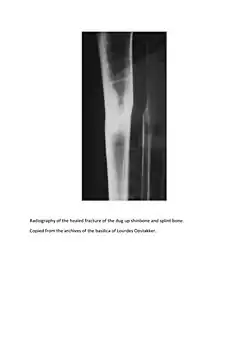

Pieter De Rudder's healed tibia X Ray